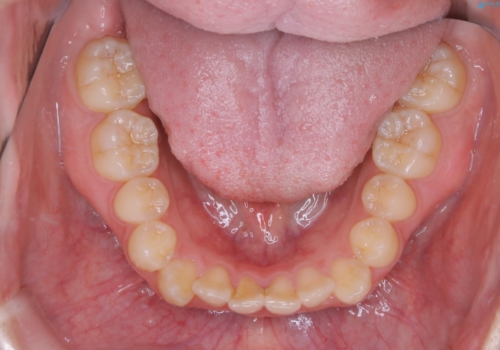

八重歯とクロスバイト:インビザライン治療

- 八重歯が気になるとの事でご相談にいらした方です。

インビザラインで綺麗に並べました。

気になっていた八重歯が綺麗になって大変喜んでいただけました。